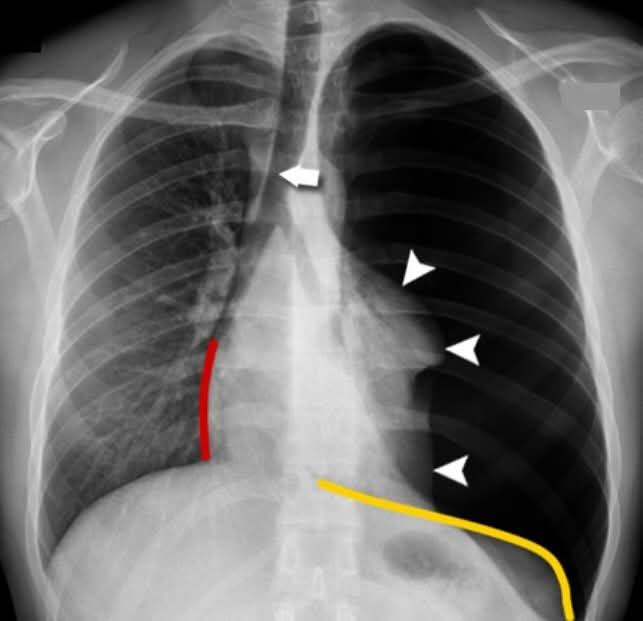

初步检查发现,努鲁发生这年轻人的左侧肺部完全听不见呼吸声,胸腔一片“寂静”。努鲁雅欣指这情况称为“气胸”。(Pneumothorax)。

经过X光扫瞄和检查,证实他患的是“张力性气胸”(Tension Pneumothorax)。

努鲁说,这是气体积聚在胸腔,压迫著心脏和右肺,如果再迟一点到医院,“可能就来不及了”。随后她紧急处理医治,同时开出止痛药后,并插入胸管排出积气。